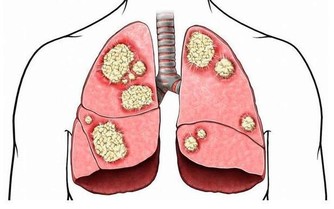

與此同時,骨質疏鬆症也被稱為“沉默的殺手”。因骨頭“變脆”,容易導致骨折。

簡單來講骨質疏鬆症是骨代謝的異常(人體內破骨細胞影響大於成骨細胞,以及骨吸收的速度超過骨形成速度)造成的。

所以,骨質疏鬆症的治療不是單純補鈣,而是綜合治療,包括提高骨量、增強骨強度和預防骨折等。也就是說,調整飲食、合理用藥、堅持鍛煉、做好防護,這些措施都要有。